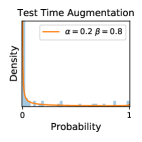

5.1 Distribution of Uncertainty Scores

Distribution of Uncertainty Scores Across Different Severity Levels As explained in Section 3, each uncertainty metric essentially defines an order/ranking among the data points. We conducted an analysis to better understand what data will be assigned high uncertainty under a particular uncertainty metric . Picking out the highest ranked data points (), we calculated the ratio of data points from each SL. Figure 4 summarizes the results as box plots for the Kaggle-DR and the Messidor-2 datasets; additional detailed statistics can be found in Table S.1 in the supplementary materials. From the plot and table, SL1 & SL2 examples account for a higher proportion among the top-ranked uncertain examples across the three ensemble methods. This finding matches our intuition that incipient disease examples (SL1 & SL2) are more likely to be considered uncertain by ensemble methods due to their ambiguity.

Comparing the three ensemble methods in Figure 4, the stacking ensemble method has the highest ratios of SL1 & SL2 data among the high-uncertainty examples it identified under both mean and var. TTA showed slightly better performance than MC-dropout but still falls behind the stacking ensemble method. Considering the fact that SL0 examples accounted for the majority of the dataset, the stacking ensemble method was much more precise (specific) in selecting truly ambiguous data points that were difficult to classify. From Figure 3, we can also see that the stacking ensemble method greatly outperformed the other two methods in finding false negatives under both mean and var uncertainty metrics.

In contrast, the MC-dropout method showed the worst overall performance among the three, as it can be seen from the high ratios of SL0 examples among the uncertain negatives in Figure 4. The histograms in Figure 2 provides another perspective to look into the phenomenon, where a decent proportion of MC-dropout model’s predictions on SL0 inputs entailed low confidence (far from 0 or 1), which from another angle explained why MC-dropout was less specific in terms of lower FNP; many no-DR inputs (i.e. SL0) were erroneously assigned high uncertainty by MC-dropout models.

It is still an open question why the evaluated MC-dropout networks signaled relatively high uncertainty on SL0 & SL3 & SL4 data that are less likely to be ambiguous. We conjecture that much of the “uncertainty” indicated by disagreement among test-time dropout samples actually reflects the stochastic nature of dropout networks rather than the real decision uncertainty associated with the data. It is worth noting that the MC-dropout model we evaluated was not weak per se; they all achieved above Area Under Curve (AUC) scores on test sets. The weakness of individual test-time samples (which explains their low-confidence predictions on SL0 & SL3 & SL4) might have been hidden when they are aggregated into an ensemble—a well-known advantage of ensemble learning. Our results suggested that the uncertainty information given by implicit ensemble methods such as MC-dropout and TTA might not be as reliable as that from explicit ensemble approaches (e.g., stacking ensembles). Similar findings on MC-dropout can be found in some previous papers [1].